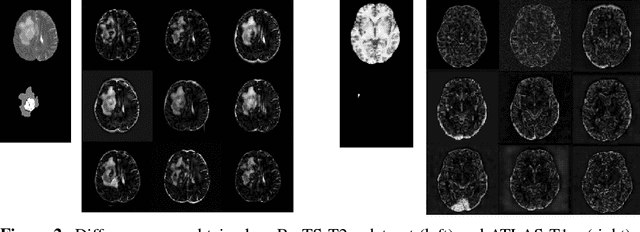

Recent advances in deep learning led to novel generative modeling techniques that achieve unprecedented quality in generated samples and performance in learning complex distributions in imaging data. These new models in medical image computing have important applications that form clinically relevant and very challenging unsupervised learning problems. In this paper, we explore the feasibility of using state-of-the-art auto-encoder-based deep generative models, such as variational and adversarial auto-encoders, for one such task: abnormality detection in medical imaging. We utilize typical, publicly available datasets with brain scans from healthy subjects and patients with stroke lesions and brain tumors. We use the data from healthy subjects to train different auto-encoder based models to learn the distribution of healthy images and detect pathologies as outliers. Models that can better learn the data distribution should be able to detect outliers more accurately. We evaluate the detection performance of deep generative models and compare them with non-deep learning based approaches to provide a benchmark of the current state of research. We conclude that abnormality detection is a challenging task for deep generative models and large room exists for improvement. In order to facilitate further research, we aim to provide carefully pre-processed imaging data available to the research community.